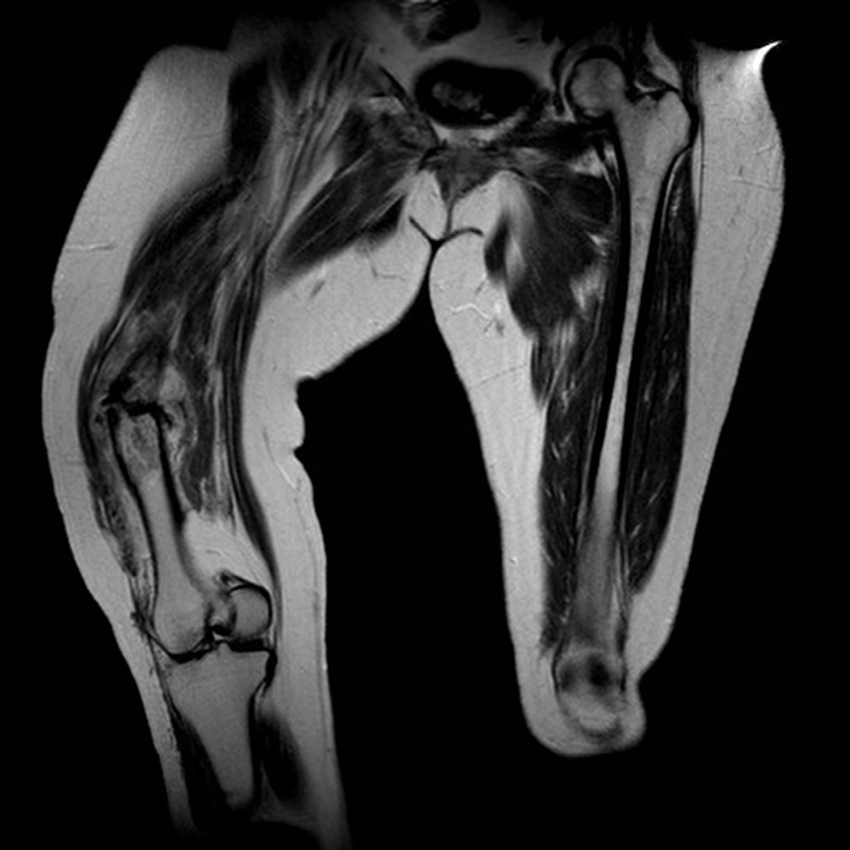

МРТ и КТ в диагностике патологического перелома

Что покажет магнитно-резонансная томография при патологическом переломе хорошо выявляет следующие анатомические признаки:

В режиме Т1 определяется зона гипоинтенсивного сигнала в губчатом веществе кости, что отражает инфильтрацию или замещение костного мозга патологической тканью.

В режиме Т2 визуализируется гиперинтенсивный сигнал в зоне отёка и перелома, а также в окружающих мягких тканях, при этом очаг может быть как однородным, так и с участками некроза или жидкости.

В режиме с подавлением сигнала от жира зона патологического сигнала становится более чёткой, хорошо дифференцируется от нормального костного мозга и окружающих структур.

В режиме с контрастированием фиксируется неравномерное усиление патологического очага, особенно в случае опухолевого происхождения перелома, при этом линия перелома может не накапливать контраст.

Могут выявляться дополнительные внутрикостные очаги поражения, утолщение или деформация кортикального слоя, а также распространение процесса на параоссальные мягкие ткани.